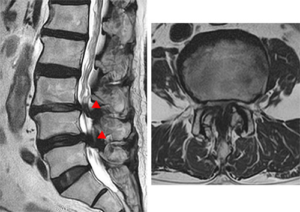

脊柱管狭窄症の症状は、馬尾神経や神経根といった末梢神経の障害によって起こります。

どんな手術にも、一定のリスクは存在します。脊柱管狭窄症の手術で代表的なものは、硬膜損傷、神経損傷、術後血腫、術後感染の4つです。

硬膜損傷とは、神経を包む膜が傷つくことです。発生頻度は2~3%程度とされていますが、顕微鏡を使用することでリスクを抑えることができます。

神経損傷は、手術器具による一時的な圧迫などで起こることがありますが、多くは時間とともに回復します。これも顕微鏡手術によって発生率は低く抑えられています。

脊柱管狭窄症の手術は、大きく分けて「除圧術」と「固定術」の2種類があります。

除圧術は、神経を圧迫している骨や靭帯を取り除き、脊柱管を広げる手術です。

体への負担が少ない低侵襲な方法として、片側侵入両側除圧術や棘突起縦割式椎弓切除術などがあります。